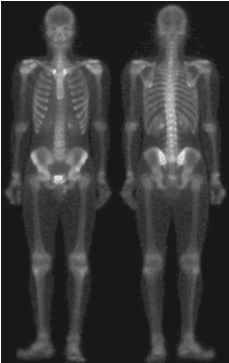

위의 사진은 뼈 감염이나 종양 같은 질환은 감지하는 전신 골격 원자력 스캔입니다. 디지털 영상 처리는 문제 지향형이기 때문에 어떤 문제를 가지느냐에 따라서 서로 다른 방향성을 가지게 됩니다. 저희는 사진에 있는 골격의 디테일을 살리는 것으로 하겠습니다. 지난 포스팅에서 따로 설명은 드리지 않았지만 라플라시안 필터는 영상의 세세한 디테일을 살리는 데 사용될 수 있으며 그래디언트 기반 필터링은 영상 내의 중요한 엣지를 찾아내는 데 도움을 줄 수 있습니다.

입력 영상 $I$에 라플라시안 필터를 적용하는 것은 라플라시안 필터를 이용한 영상 샤프닝의 시작이라고 하였습니다. 하지만 위의 그림을 보면 영상 내의 노이즈가 꽤 많이 있기 때문에 샤프닝된 영상은 노이즈가 많을 것이라고 예상할 수 있습니다.